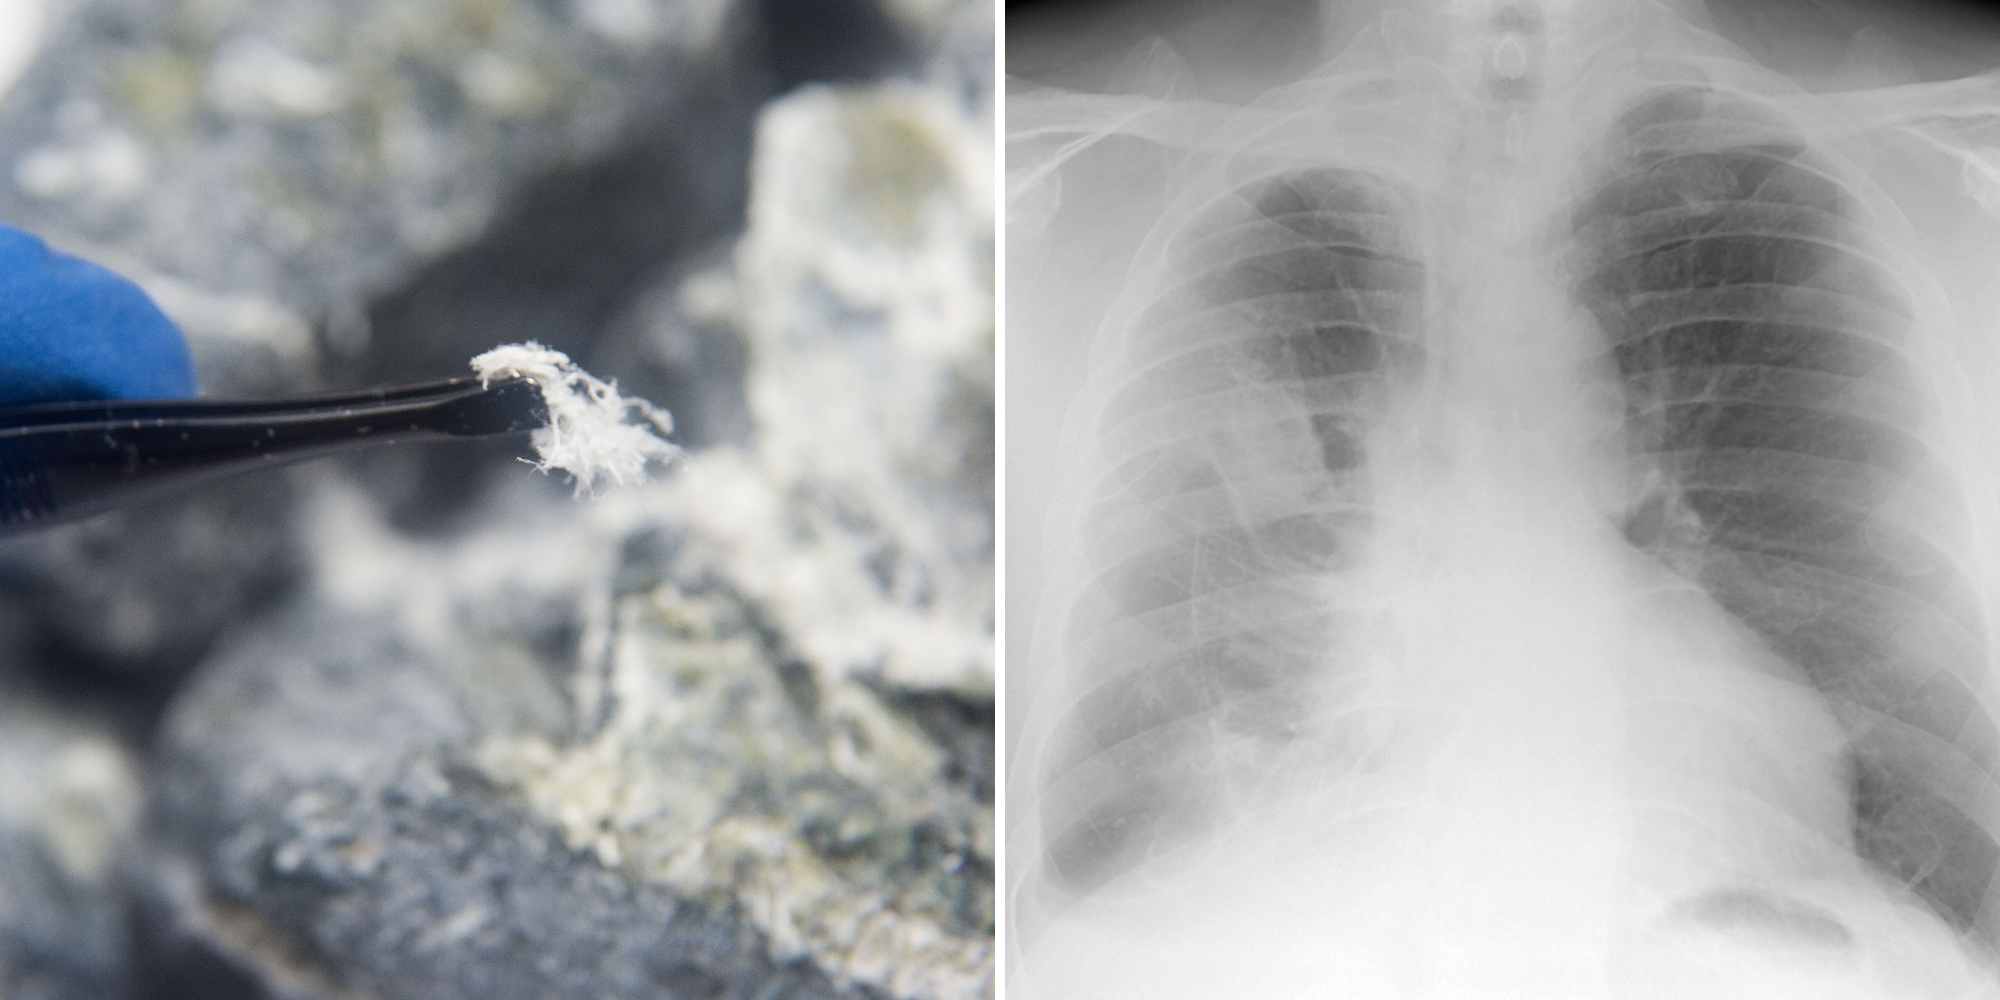

厚生労働省が2025年9月16日に発表した「人口動態統計(確定数)」に基づき、令和6年(2024年)の中皮腫による死亡者数が1,562名であったことが明らかになりました。中皮腫は、主に石綿(アスベスト)の吸入が原因で発症する悪性腫瘍であり、この数字は日本の公衆衛生における重要な指標の一つです。

令和6年の中皮腫死亡者数は1,562名でした。内訳は、男性が1,266名、女性が296名と、男性が女性の4倍以上にのぼります。これは、かつてアスベストを大量に使用していた建築業や製造業など、特定の産業に従事する機会が男性に偏っていた歴史を反映しています。